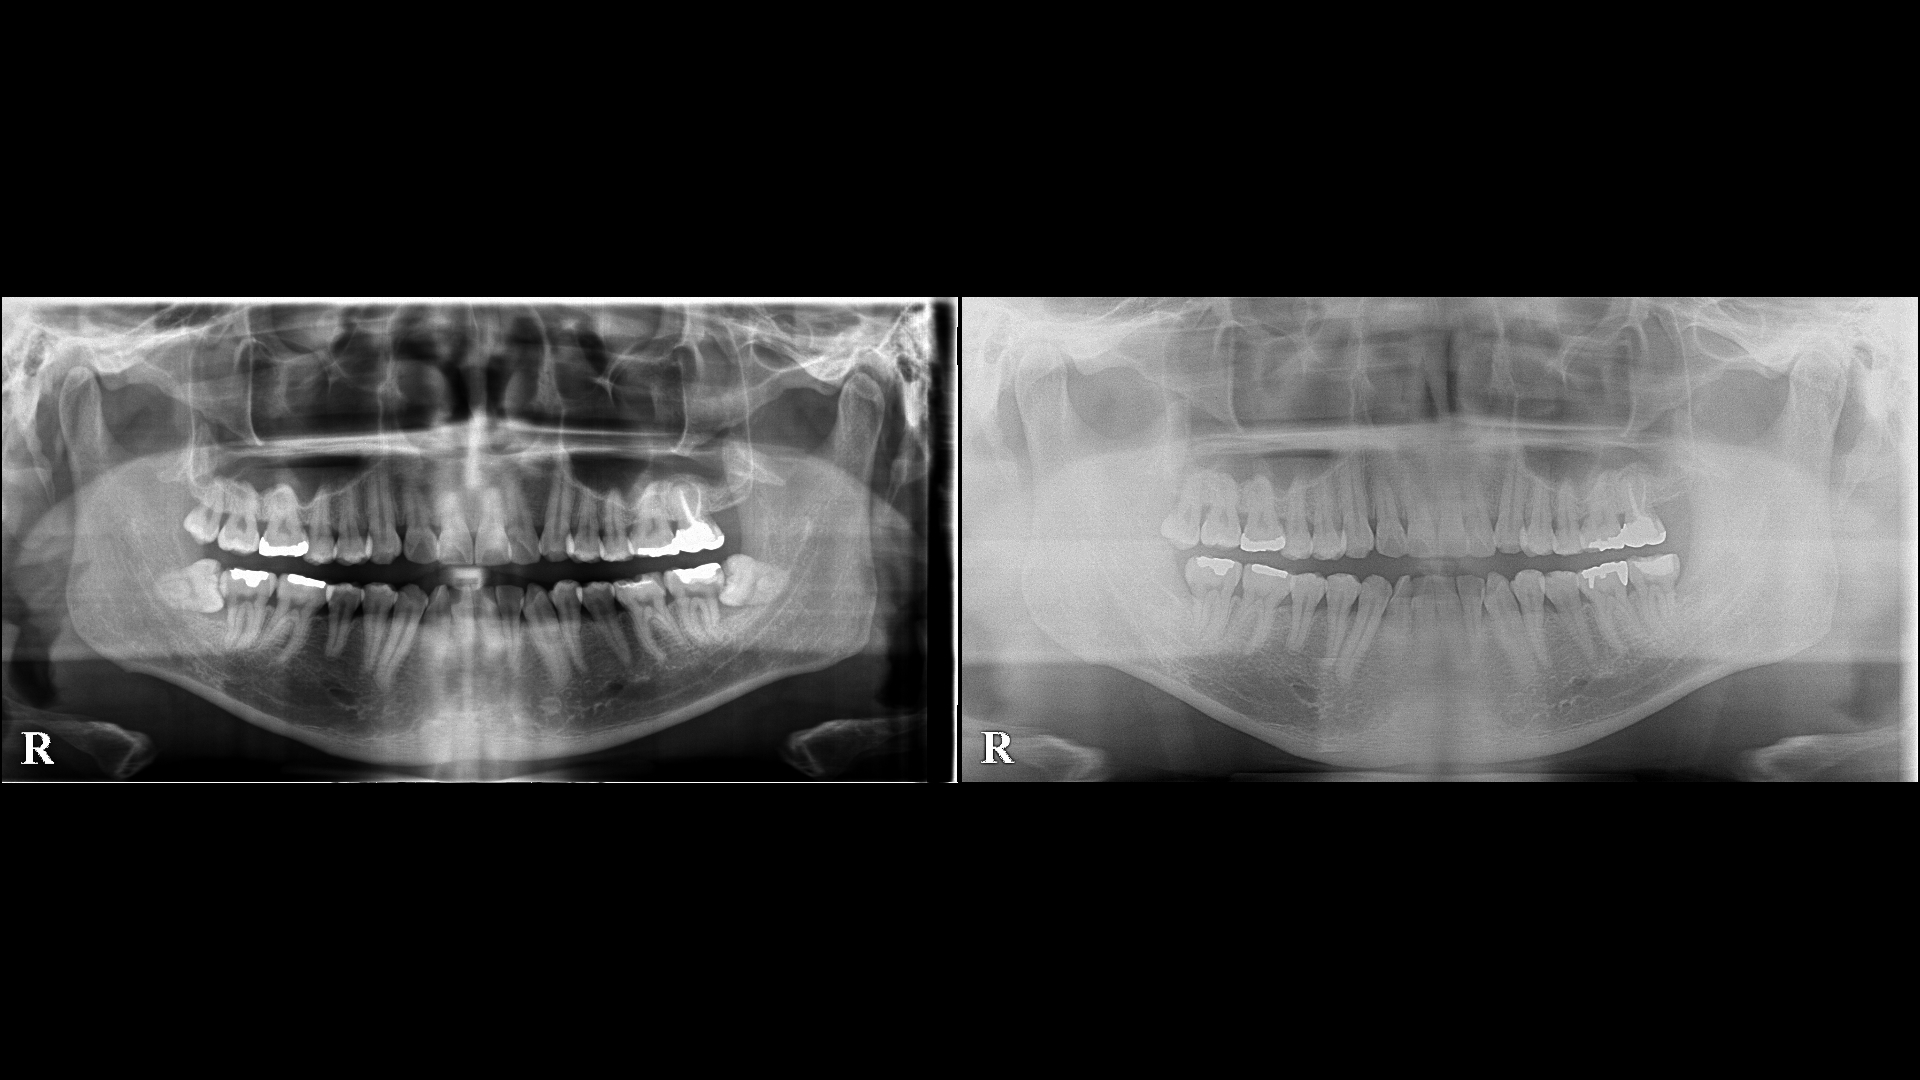

左側の写真は親知らずを抜く前の写真です。

左下の親しらずは横向きに生えており、前の歯の隣接面が虫歯になっています。

親知らずを抜いて虫歯の治療が必要です。

右の写真は抜歯後の写真です。

ブラッシングが容易にできる環境になっています。